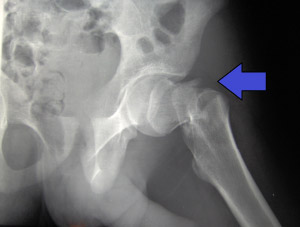

Las fracturas de cadera

Actualmente, a nivel mundial, las fracturas de cadera se encuentran entre las 10 principales causas de discapacidad en adultos. Más concretamente, para las fracturas desplazadas del cuello femoral, sigue habiendo

Osteopetrosis

Hemos operado por segunda vez una paciente con OSTEOPETROSIS enfermedad rara que se presenta desde el nacimiento y afecta a 1 persona entre 20.000 nacimientos y 1 entre 200.000 adultos.